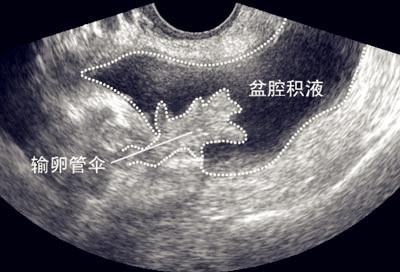

5 .盆腔积液

盆腔积液常见于女性,当盆腹腔脏器有少量渗出液、漏出液或破裂出血时,液体会首先聚积在盆腔,从而形成盆腔积液,月经就有可能造成盆腔积液,按下去有水声,

但盆腔积液可分为生理性盆腔积液和病理性盆腔积液两种。生理学盆腔积液属于正常范畴,病理性盆腔积液可发生在盆腔炎、附件炎或子宫内膜异位症之后,为盆腔炎的主要影像学特征。